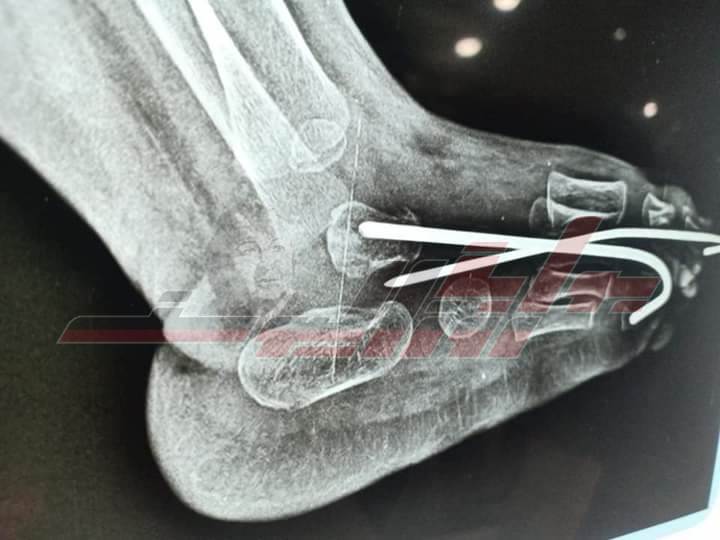

وقام الفريق الطبي بمستشفى حوش عيسى بقيادة إكرامى الشربتلي مدير عام المستشفى والدكتور نصر القزاز رئيس قسم العظام ورئيس الهيئة الطبية و الدكتور محمود عطية مقاوي مدرس التخدير بجامعة الإسكندرية والفريق المعاون تحت إشراف الدكتور محمود طلحة - وكيل الوزارة والدكتور حمودة الجزار وكيل مديرية الصحة بتقويم وتصليح الكاحل الخلقي العمودي Congenital Vertical Talus والذي ينتج عنه اعوجاج شديد جداً في القدم والكاحل لطفل يبلغ من العمر عاما.